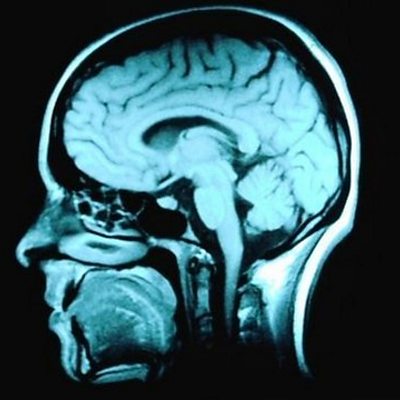

The ÃÛÑ¿´«Ã½'s science reporter Rebecca Morelle discovers the benefits of 'deep learning'.